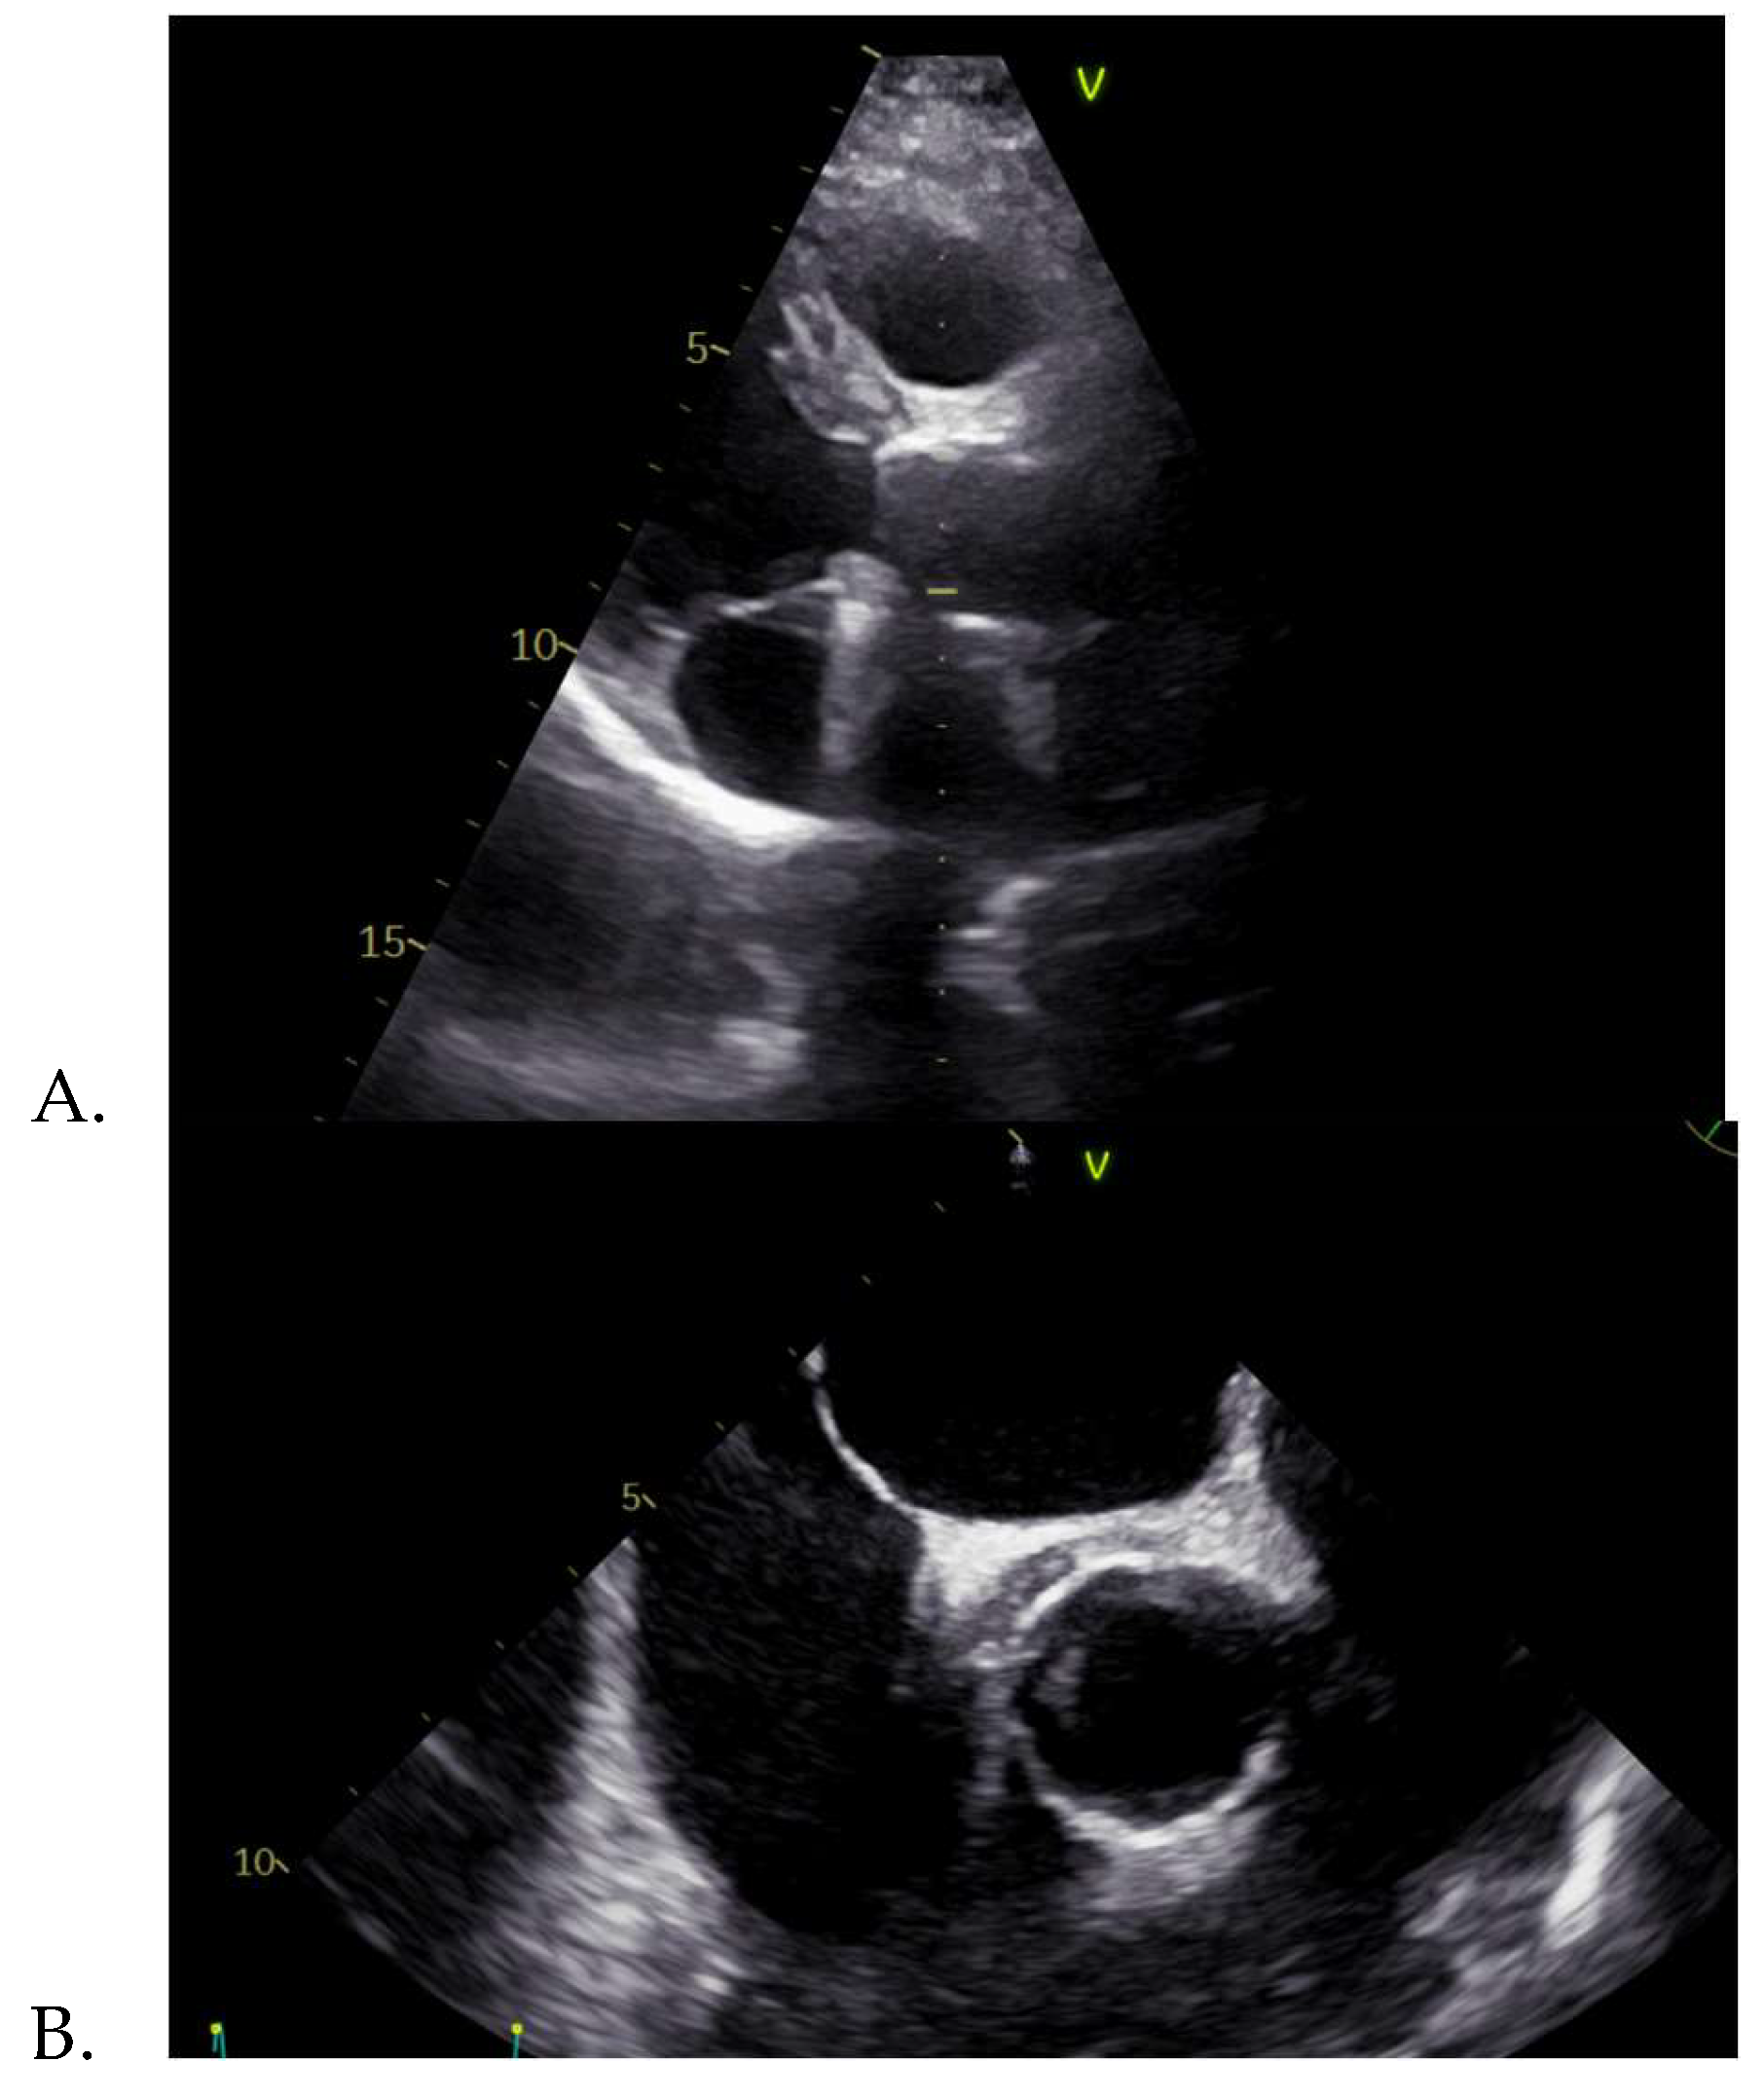

In June 2024, the patient was admitted in our clinic, accusing intermittent febrile syndrome with subfebrile onset for about 3 months, accompanied by vertigo. The medical examination revealed normal vital signs, pale skin and the cardiac examination highlighted a systolic murmur, heard loudest at aortic area, closing click on aortic area. The ECG was normal. The pathological blood samples collected at admission revealed an inflammatory syndrome, i.e. highly elevated ESR and C- reactive protein, with positive procalcitonin. The transthoracic echocardiography showed an apparently normal mechanical prosthesis in aortic position, mild intraprosthetic aortic regurgitation, mild mitral regurgitation, mild functional tricuspid regurgitation, mild secondary pulmonary hypertension and a roughly 12 mm, echo-dense mass surrounding the ascending aorta, this image being also found on the transesophageal echocardiography. Transesophageal echocardiography is an investigation that provides additional information on heart morphology, usually being used for a better view of the left atrium and the left atrial appendage in order to detect thrombi, but in our case it was used for a better acquisition of the aortic valve [23,24].

Figure 1. A. Transthoracic and B. Transesophageal echocardiography showing an echo-dense mass surrounding the ascending aorta.